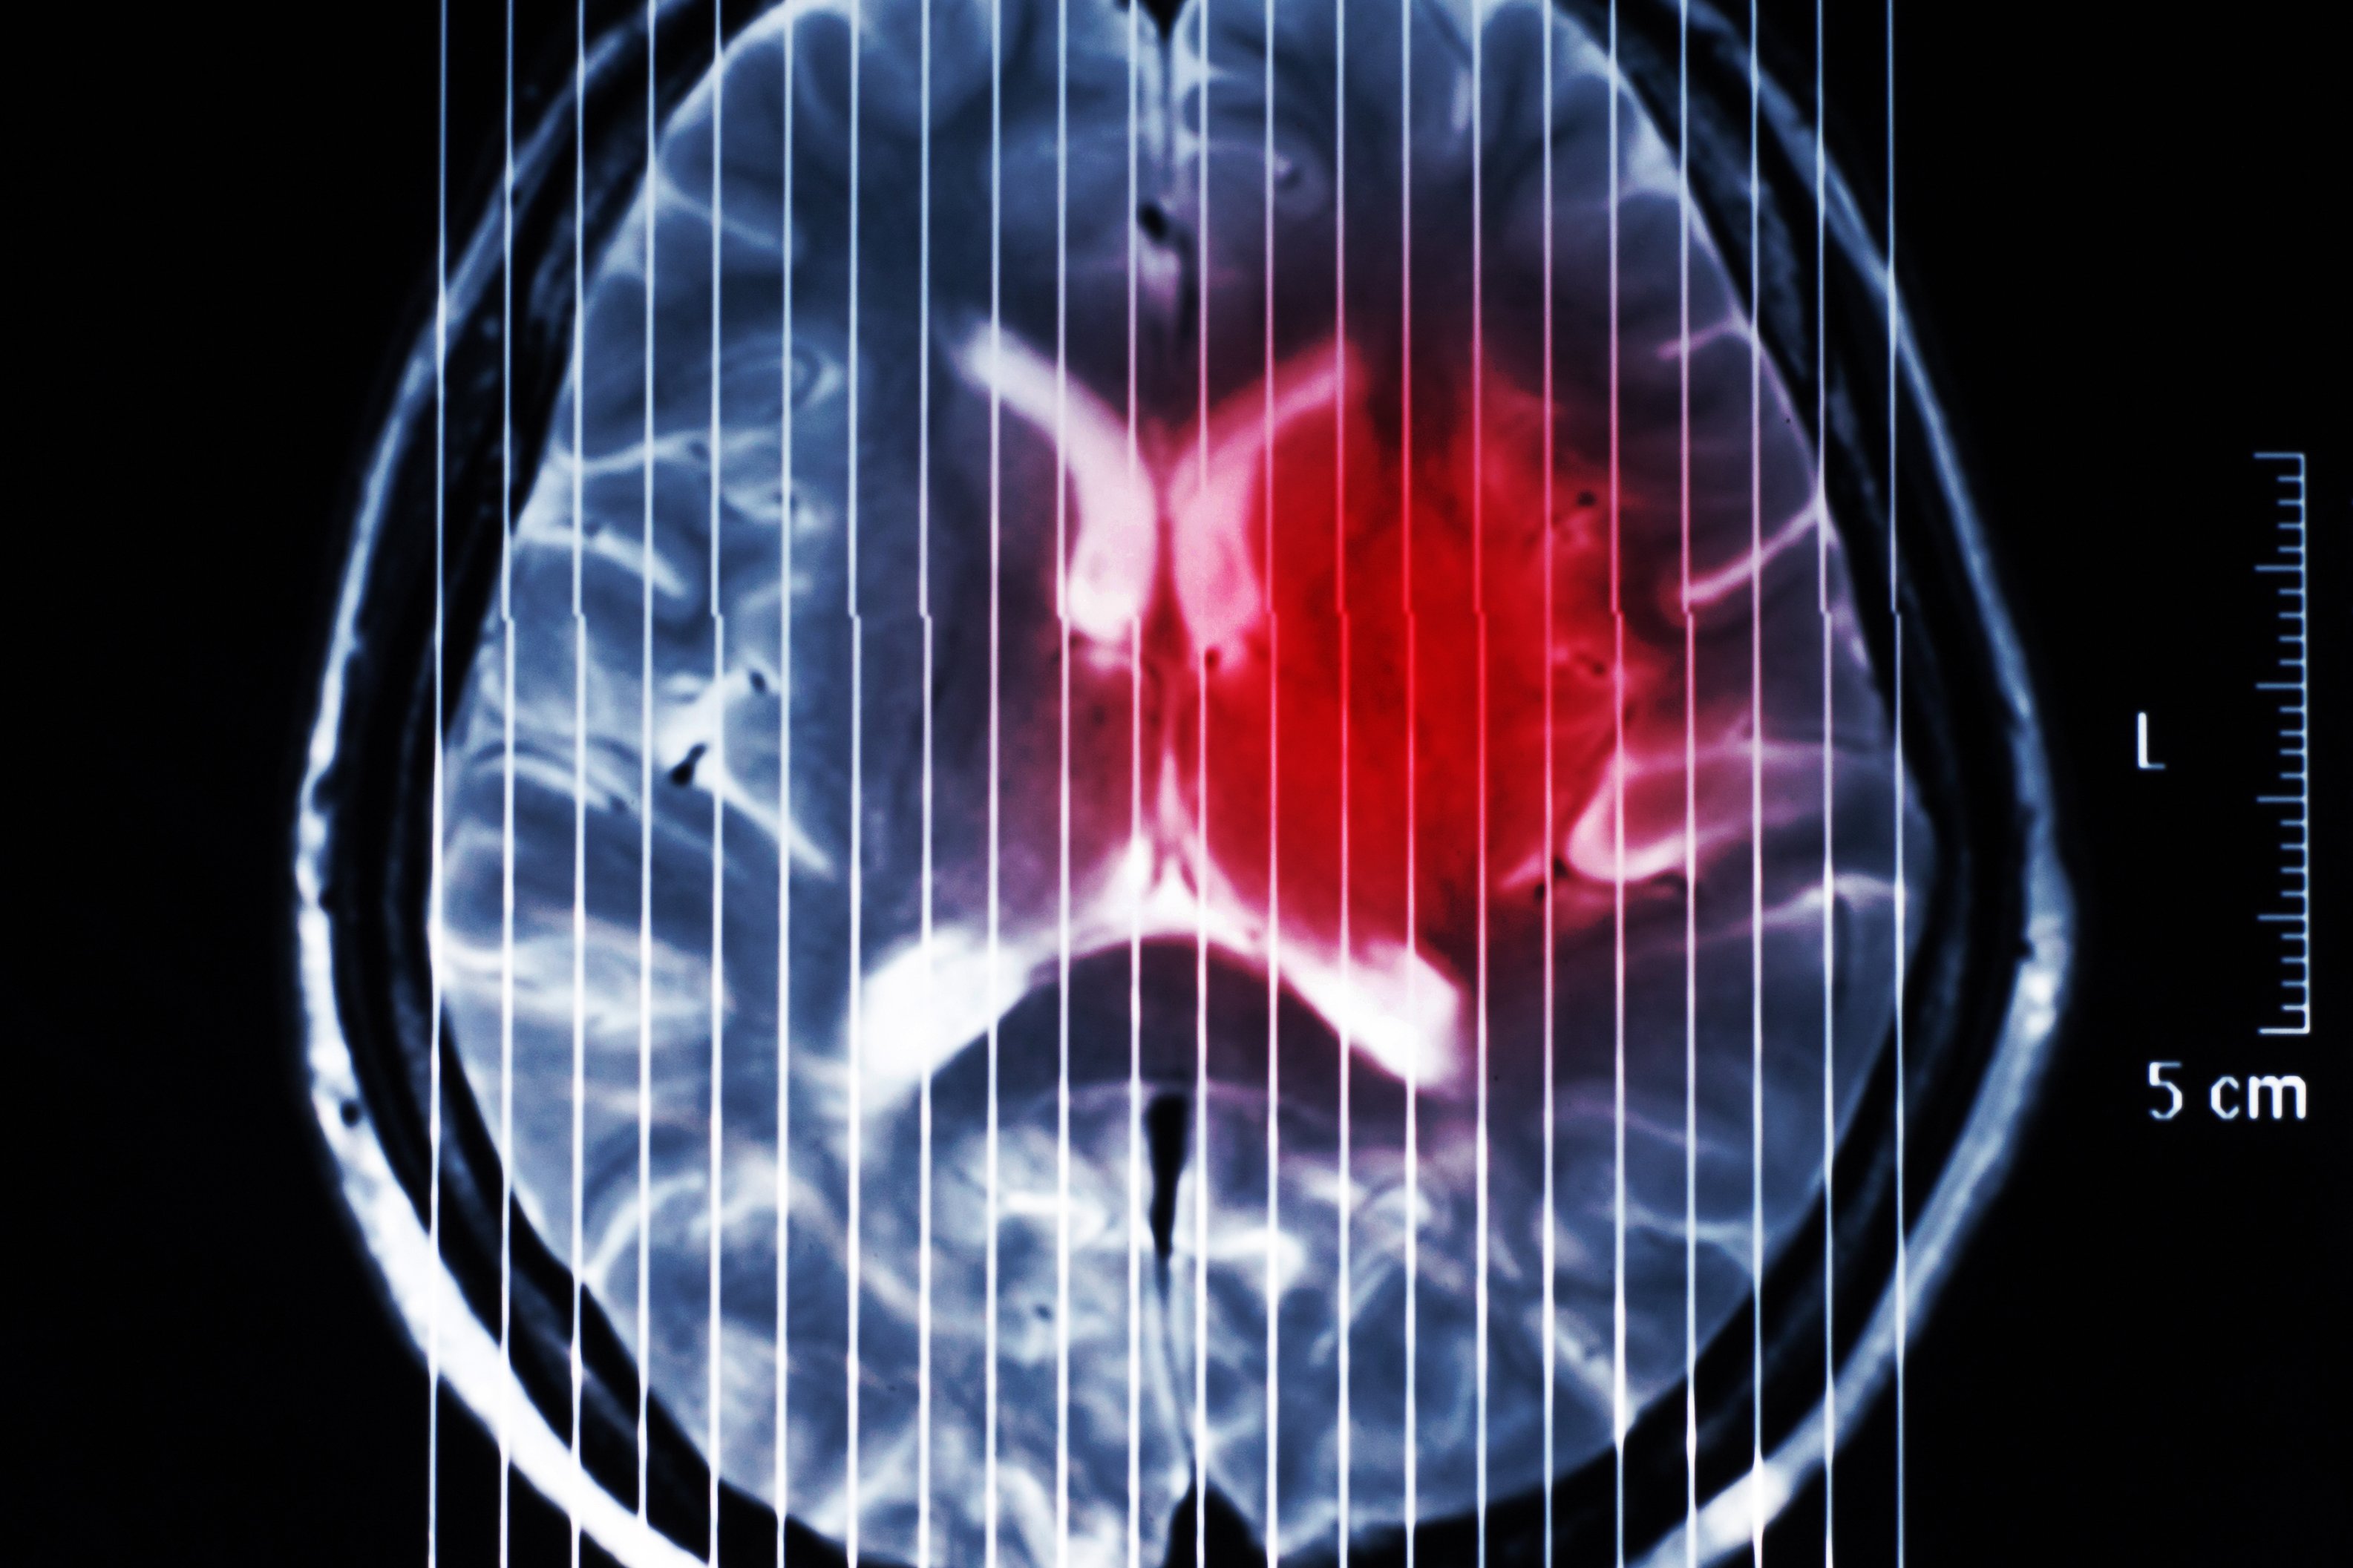

(Wien, 17-12-2024) Das diffuse hemisphärische Gliom (DHG) ist eine Gehirntumorerkrankung bei Kindern, Jugendlichen und jungen Erwachsenen mit einer Überlebensprognose von durchschnittlich weniger als zwei Jahren und eingeschränkten Therapieoptionen. Ein Forschungsteam von MedUni Wien und AKH Wien identifizierte erhöhten Stress durch gezielte Erbsubstanz-(DNA)-Brüche unter gleichzeitiger Hemmung der DNA-Reparatur in der Tumorzelle als vielversprechenden Therapieansatz. Die Studie ist aktuell im Fachjournal „Neuro-Oncology“ erschienen.

Die zugrundeliegenden molekularen Mechanismen des DHG wurden erstmals vor gut zehn Jahren charakterisiert. Das DHG wird aufgrund dieser spezifischen Charakteristika mittlerweile als eigenständige Hirntumorart gelistet. Bisher konnte dieses Wissen aber nicht in effizientere Therapiemöglichkeiten umgesetzt werden. Die aktuelle Forschungsarbeit unter der Leitung von Johannes Gojo (Universitätsklinik für Kinder- und Jugendheilkunde) und Walter Berger (Zentrum für Krebsforschung) konnte zeigen, dass die Tumorzellen einen speziellen Mechanismus nutzen, um „unsterblich“ zu werden. Dieser Mechanismus geht aber mit erhöhtem Stress aufgrund von vermehrten Erbsubstanz (DNA)-Schäden einher. Diese „Verletzlichkeit“ identifizierte die Forschungsgruppe als neuen therapeutischen Ansatz und zeigte, dass das gezielte Auslösen weiterer DNA-Schäden unter gleichzeitiger Hemmung der DNA-Reparatur einen vielversprechenden Therapieansatz für diese aggressive Tumorart des Gehirns darstellt.